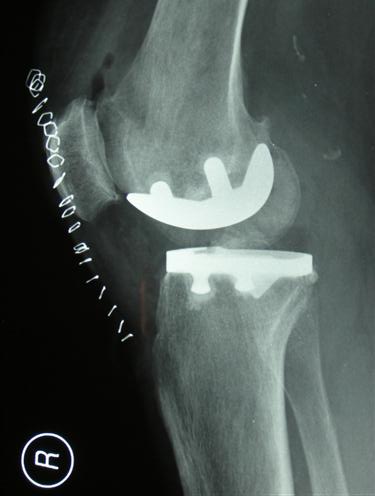

TKA

Total knee replacement has been the standard procedure to deal surgically with severe osteoarthritis of the knee. This involves replacement of the joint surfaces of the femur (thighbone) and the tibia (shinbone). Replacing the joint surface of the patella (knee cap) is optional, and a point of ongoing discussion.

Results of this procedure have been very good with 90-95% of these devices still functioning well at 10 years. However, it is a fairly involved procedure. Complications occur, which can be very serious (see consent TKA).

After Total Knee Replacement, non-cemented:

2/ Example 2: Unicompartmental knee replacement (Oxford-cemented) and Total Knee replacement (cemented)